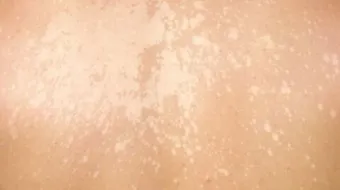

تتعرض البشرة للكثير من المشاكل الصحية وهي شائعة للغاية، وتصيب غالباً أصحاب البشرة الداكنة أو السمراء، وتظهر لدى الأطفال والمراهقين أكثر من غيرهم، وقد تظهر بشكل مفاجئ أو تدريجي، وقد تكون دائمة أو مؤقتة، وهناك العديد من المسببات لهذه البقع، فقد يكون عدوى أو حساسية أو اضطراب في جهاز المناعة لدى الإنسان، لذا يجب استشارة الطبيب للتعرف على أسبابها.

ما سبب ظهور بقع بيضاء على الجلد

البهاق

هو أحد أمراض المناعة الذاتية، ويعتبر مرض جلدي غير معدٍ، حيث تهاجم خلايا الجهاز المناعي الجسم، ويكون تركيزها على خلايا الميلانين المسؤولة عن صبغة الجلد، التي تعطي البشرة لونها الحقيقي، وتتميز بقع البهاق بلونها الأبيض الناصع، وتكون حوافها داكنة اللون، وعلاج البهاق يكون باستخدام الأشعة فوق البنفسجية في بعض الحالات، أو التعرض لأشعة الشمس مع استخدام الكريمات الخاصة بالجلد، وقد يلجأ الأطباء إلى إزالة جميع الخلايا الصبغية من الجلد، ثمّ توحيد لون الجلد، وذلك في حالة زيادة نسبة البهاق على 50% من لون الجلد.

التينيا الملونة

وهو مرض فطري يصيب الجلد، وتكون بدايته ببقع فاتحة اللون أو أغمق من لون الجلد، ويبدأ بالانتشار من الرأس إلى الرقبة، ثمّ إلى الأيدي، حتى الوصول للجسم كله، ويكون علاجه عن طريق مراهم خاصة توضع على الجلد، مع الشامبوهات الطبية، ويجب متابعة الحالة من الطبيب المختص لحين الشفاء.

النخالة البيضاء

وهي نوع من أنواع الأكزيما، وتكون على شكل بقع وردية عليها قشور، وتنتشر في الجلد، حتى تتحول إلى لون فاتح، وتكون أكثر وضوحاً في ضوء الشمس، ويمكن للطبيب تشخيص النخالة البيضاء بسهولة، ويعتبر سوء التغذية والنقص في فيتامين "A"، أو وجود ديدان معوية في البطن، هي أسباب مهمة في ظهور بقع النخالة البيضاء.

سوء التغذية

وهي مشكلة شائعة في مجتمعاتنا، وقد تظهر البقع البيضاء على الجلد في عدة حالات ومنها سوء التغذية، وعند النقص لفيتامين C و A في الجسم، مما يتطلب الحصول على طعام صحي وغني بالعناصر الكاملة، ويكون علاجها باستخدام كريمات خاصة لعلاج البقع والتي تقوم بتجديد خلايا الجلد بسرعة.